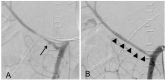

Postpancreaticoduodenectomy (PD) bleeding, which is reported to occur in 5-7%, is a major complication that often causes life-threatening secondary events. A transarterial catheter technique with coil embolization is a widespread procedure that could potentially cause massive hepatic infarction and subsequent sepsis with hepatic abscess, which can be a fatal complication. Here, we introduce a new transarterial technique that uses a hemostat with a stent graft, which successfully rescued a patient had suffered post-PD bleeding.